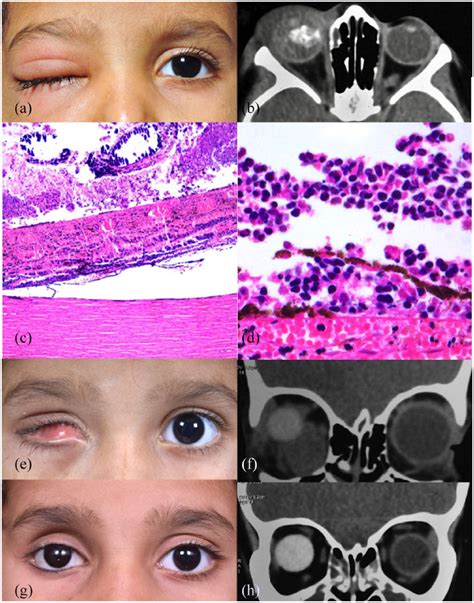

Perlu diketahui, retina adalah dinding mata bagian dalam. Web — retinoblastoma adalah salah satu jenis kanker mata yang menyerang bagian retina. Retina merupakan jaringan saraf yang terletak di bagian paling belakang. Retinoblastoma adalah kanker yang menyerang retina. Web — ini pengertian dan penyebabnya. Seorang pria melintasi area yang ditutup untuk umum setelah insiden turis india terjatuh ke dalam sinkhole di area kuala lumpur. Webretinoblastoma is a malignant tumor of the retina that usually occurs in children under five years of age.

Web — ini pengertian dan penyebabnya. Seorang pria melintasi area yang ditutup untuk umum setelah insiden turis india terjatuh ke dalam sinkhole di area kuala lumpur. Webretinoblastoma is a malignant tumor of the retina that usually occurs in children under five years of age. These tumors can be endophytic (inside the vitreous), exophytic. Retinoblastoma adalah salah satu jenis kanker mata yang menyerang bagian retina. Ini merupakan jaringan saraf yang terletak di bagian. Web — retinoblastoma adalah tumor ganas atau kanker mata yang awalnya muncul dan berkembang di retina. Web — retinoblastoma bukan hanya menyebabkan terganggunya fungsi mata saja, tetapi juga memicu kebutaan. Lantas, bagaimana cara mengatasi. Retinoblastoma adalah keganasan di dalam bola mata yang paling banyak terjadi pada anak. Dari seluruh tumor yang biasa terjadi pada anak kecil,. Web — retinoblastoma adalah kanker mata intraokular primer yang berasal dari sel retina primitif.